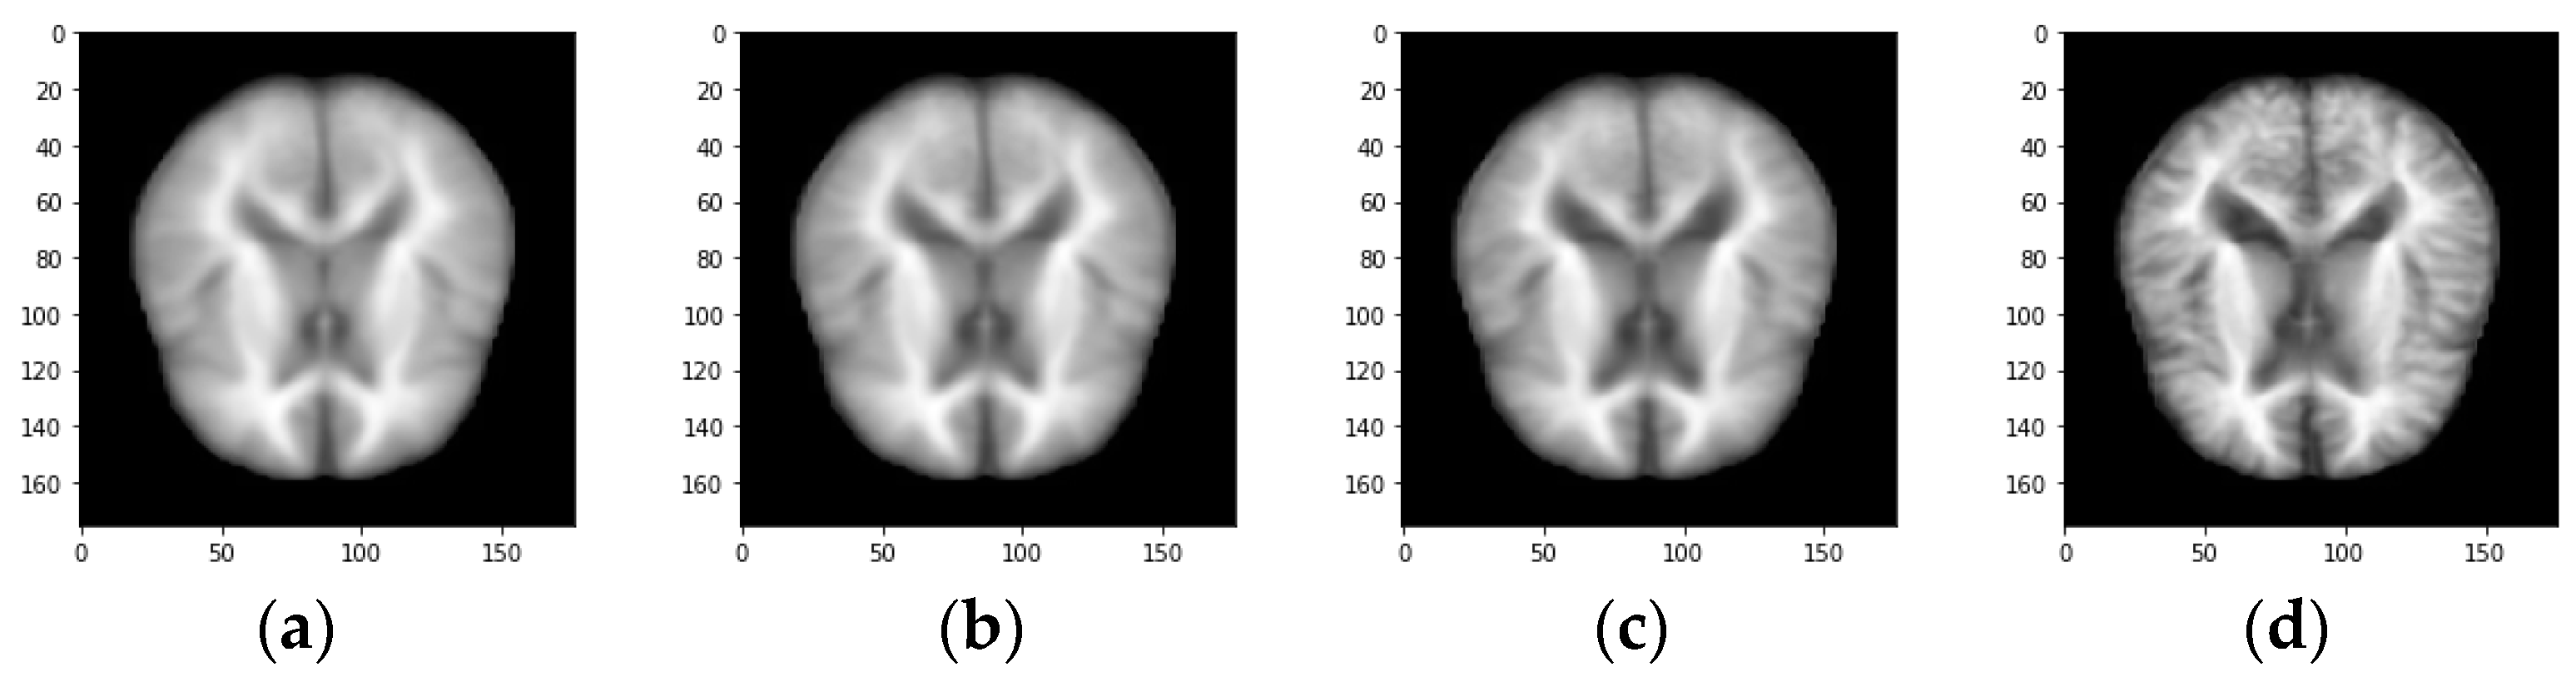

Figure 3.

Sample MRI image demented categories. (a) Non-demented image (b) Very mild demented image (c) Mild demented (d) Moderate demented.